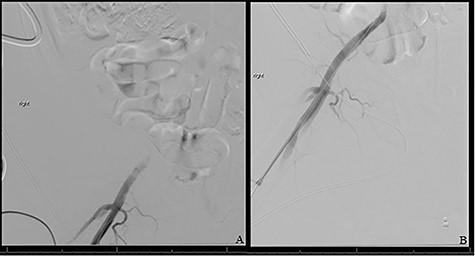

A repeat intravascular ultrasound showed bilateral iliac vein stenosis at the level of the IVC bifurcation. Thus, we deployed 14-mm Wallstents in both iliac veins into the distal IVC. A complete venogram showed adequate flow through the external and common iliac systems bilaterally (Fig. 1). The total operating time was 6 h.

(A) Shows initial retrograde angiogram of right common femoral artery with occlusion at the level of the EIA. (B) demonstrates restoration of flow postangioplasty and stenting.